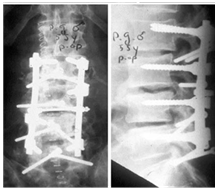

Limited Intervention by Vertebral Augmentation and TLSO & Medical TTT

- 76Years old lady attended with low and mid back pain over the last three months.

- Has a history of L4-L5 cage fusion 15 years before.

- Radiological examination shows:

- Loss of Lumber Lordosis.

- High Degree of Dorso- Lumber kyphosis.

- Wedge compression fractures at D12 &D11.

- Treatment:

- Vertebral Augmentation.

- TLOS Brace.

- Alendronate drugs for her osteoporosis (Figure 8).

Figure 8 Limited intervention by vertebral augmentation and TLSO & Medical ttt.